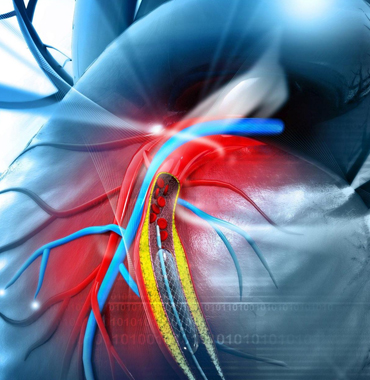

Dr Satya Gupta is known for providing best cardiac consultation and excellent outcome. One of the finest interventional cardiologist of the country with excellent academic and educational background. He is founder of “Radial angiography and angioplasty program”in the Heart Care Clinic group (HCC) in the year 2006.

One of the finest interventional cardiologist

Dr Satya Gupta’s practice is based on recent cardiology guideline and he strongly believes in honest and ethical cardiac practice. Dr Satya Gupta has obtained highest level of qualification in the field of cardiology.